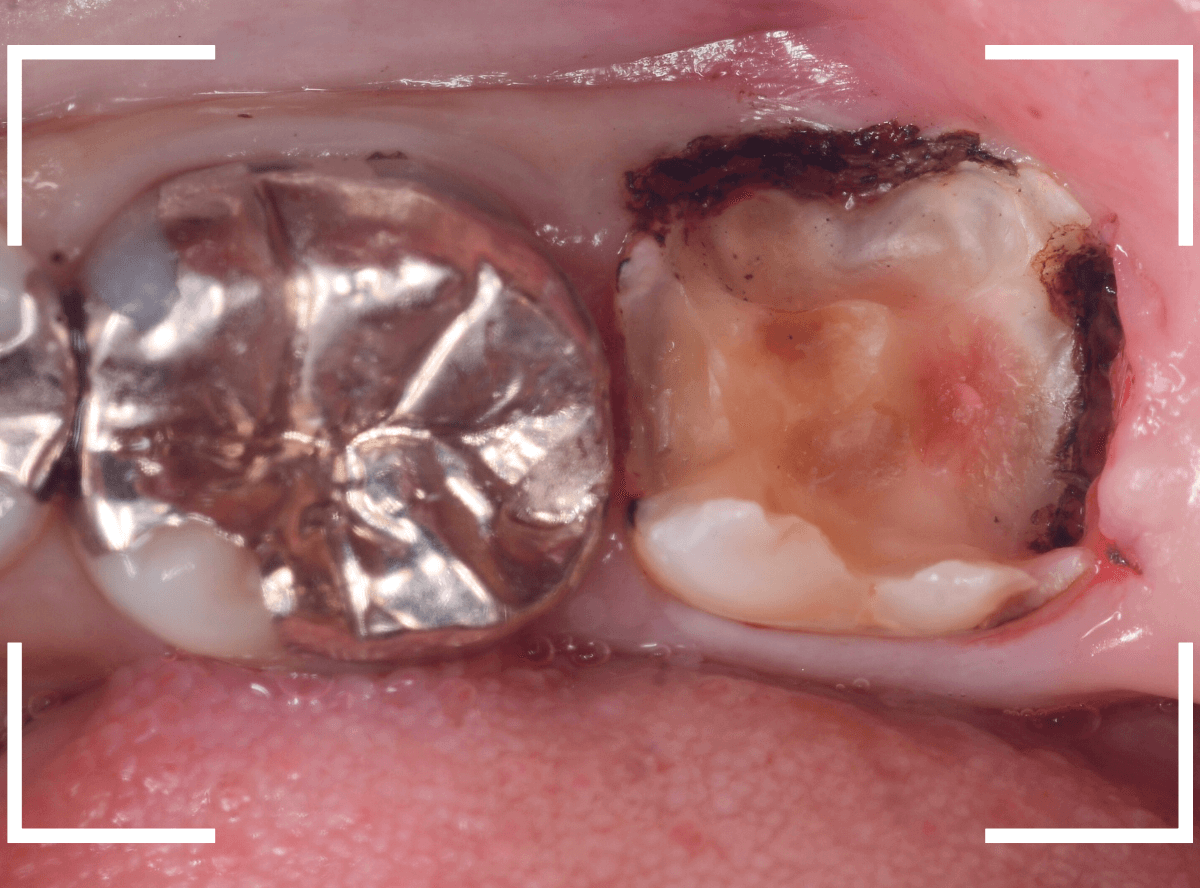

Case.14 インレーの下の歯肉まで広がった虫歯

「下の奥歯が噛むと痛む」という症状で来院された患者さんのケースです。

お口の中の状態を確認すると、奥歯の端に穴が開いているのが見えます。

ここかな?

レントゲン写真で確認します。

やはり、奥歯の端が大きな虫歯になっています。

青いラインが歯の神経、赤いラインが虫歯です。

レントゲン写真上では虫歯が神経まで達しているように見えます。

これは、神経を取らないとダメかもしれません。

中のお薬も慎重に外して虫歯を除去します。

虫歯が深く、歯肉の下まで浸食していましたので、歯肉を部分切除し、虫歯を全て除去したところで、奇跡的に神経スレスレの状態でとどまっていました。

何とも言えませんが、神経を残せる可能性が出てきました。

虫歯が神経まで達していなくても、治療前から自発痛(何もしなくても痛い)があれば、神経をとらなければいけません。

今回は、そこまでの症状がありませんでしたので、患者さんと相談の上、神経を取らずに残す方法で様子を見る事になりました。

痛みが出ませんように。。。